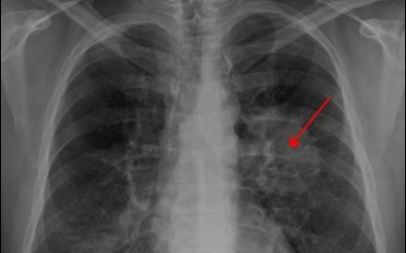

이번 기사에서는 폐암 초기 증상에 대해 자세히 정리해 알려 드리겠습니다 . 폐암은 국내암 사망률 1 위로, 과거에는 흡연이 폐암의 주된 원인 이었지만 , 현재는 비흡연 폐암 환자도 대폭 증가했습니다 . 폐암은 의학 기술로 발달하여 생존율이 높아지고 있습니다 . 폐암의 초기 증상은 무엇인가를 알아보겠습니다.

3. 폐암 초기 증상 - 잔기침

평소 보다 잔기침이 많아지면 위험하다고 합니다 . 폐에 문제가 생겼다는 신호 중 하나 라고 합니다 . 그리고 폐암은 초기 발견이 어렵다고 하므로 , 보다 세심한 관찰이 필요한 것 같습니다 .